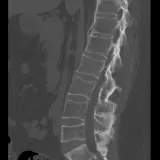

MSK Radiographs